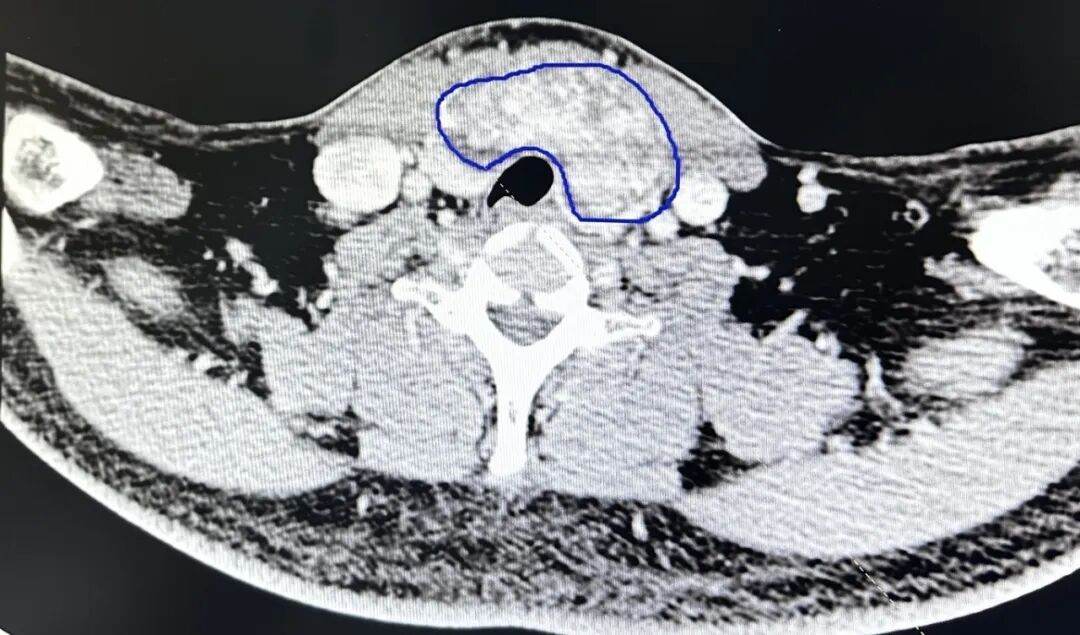

自己甲狀腺峽部的腫塊

達到了6.5厘米

而且腫塊緊緊的包圍著

頸部的神經和血管